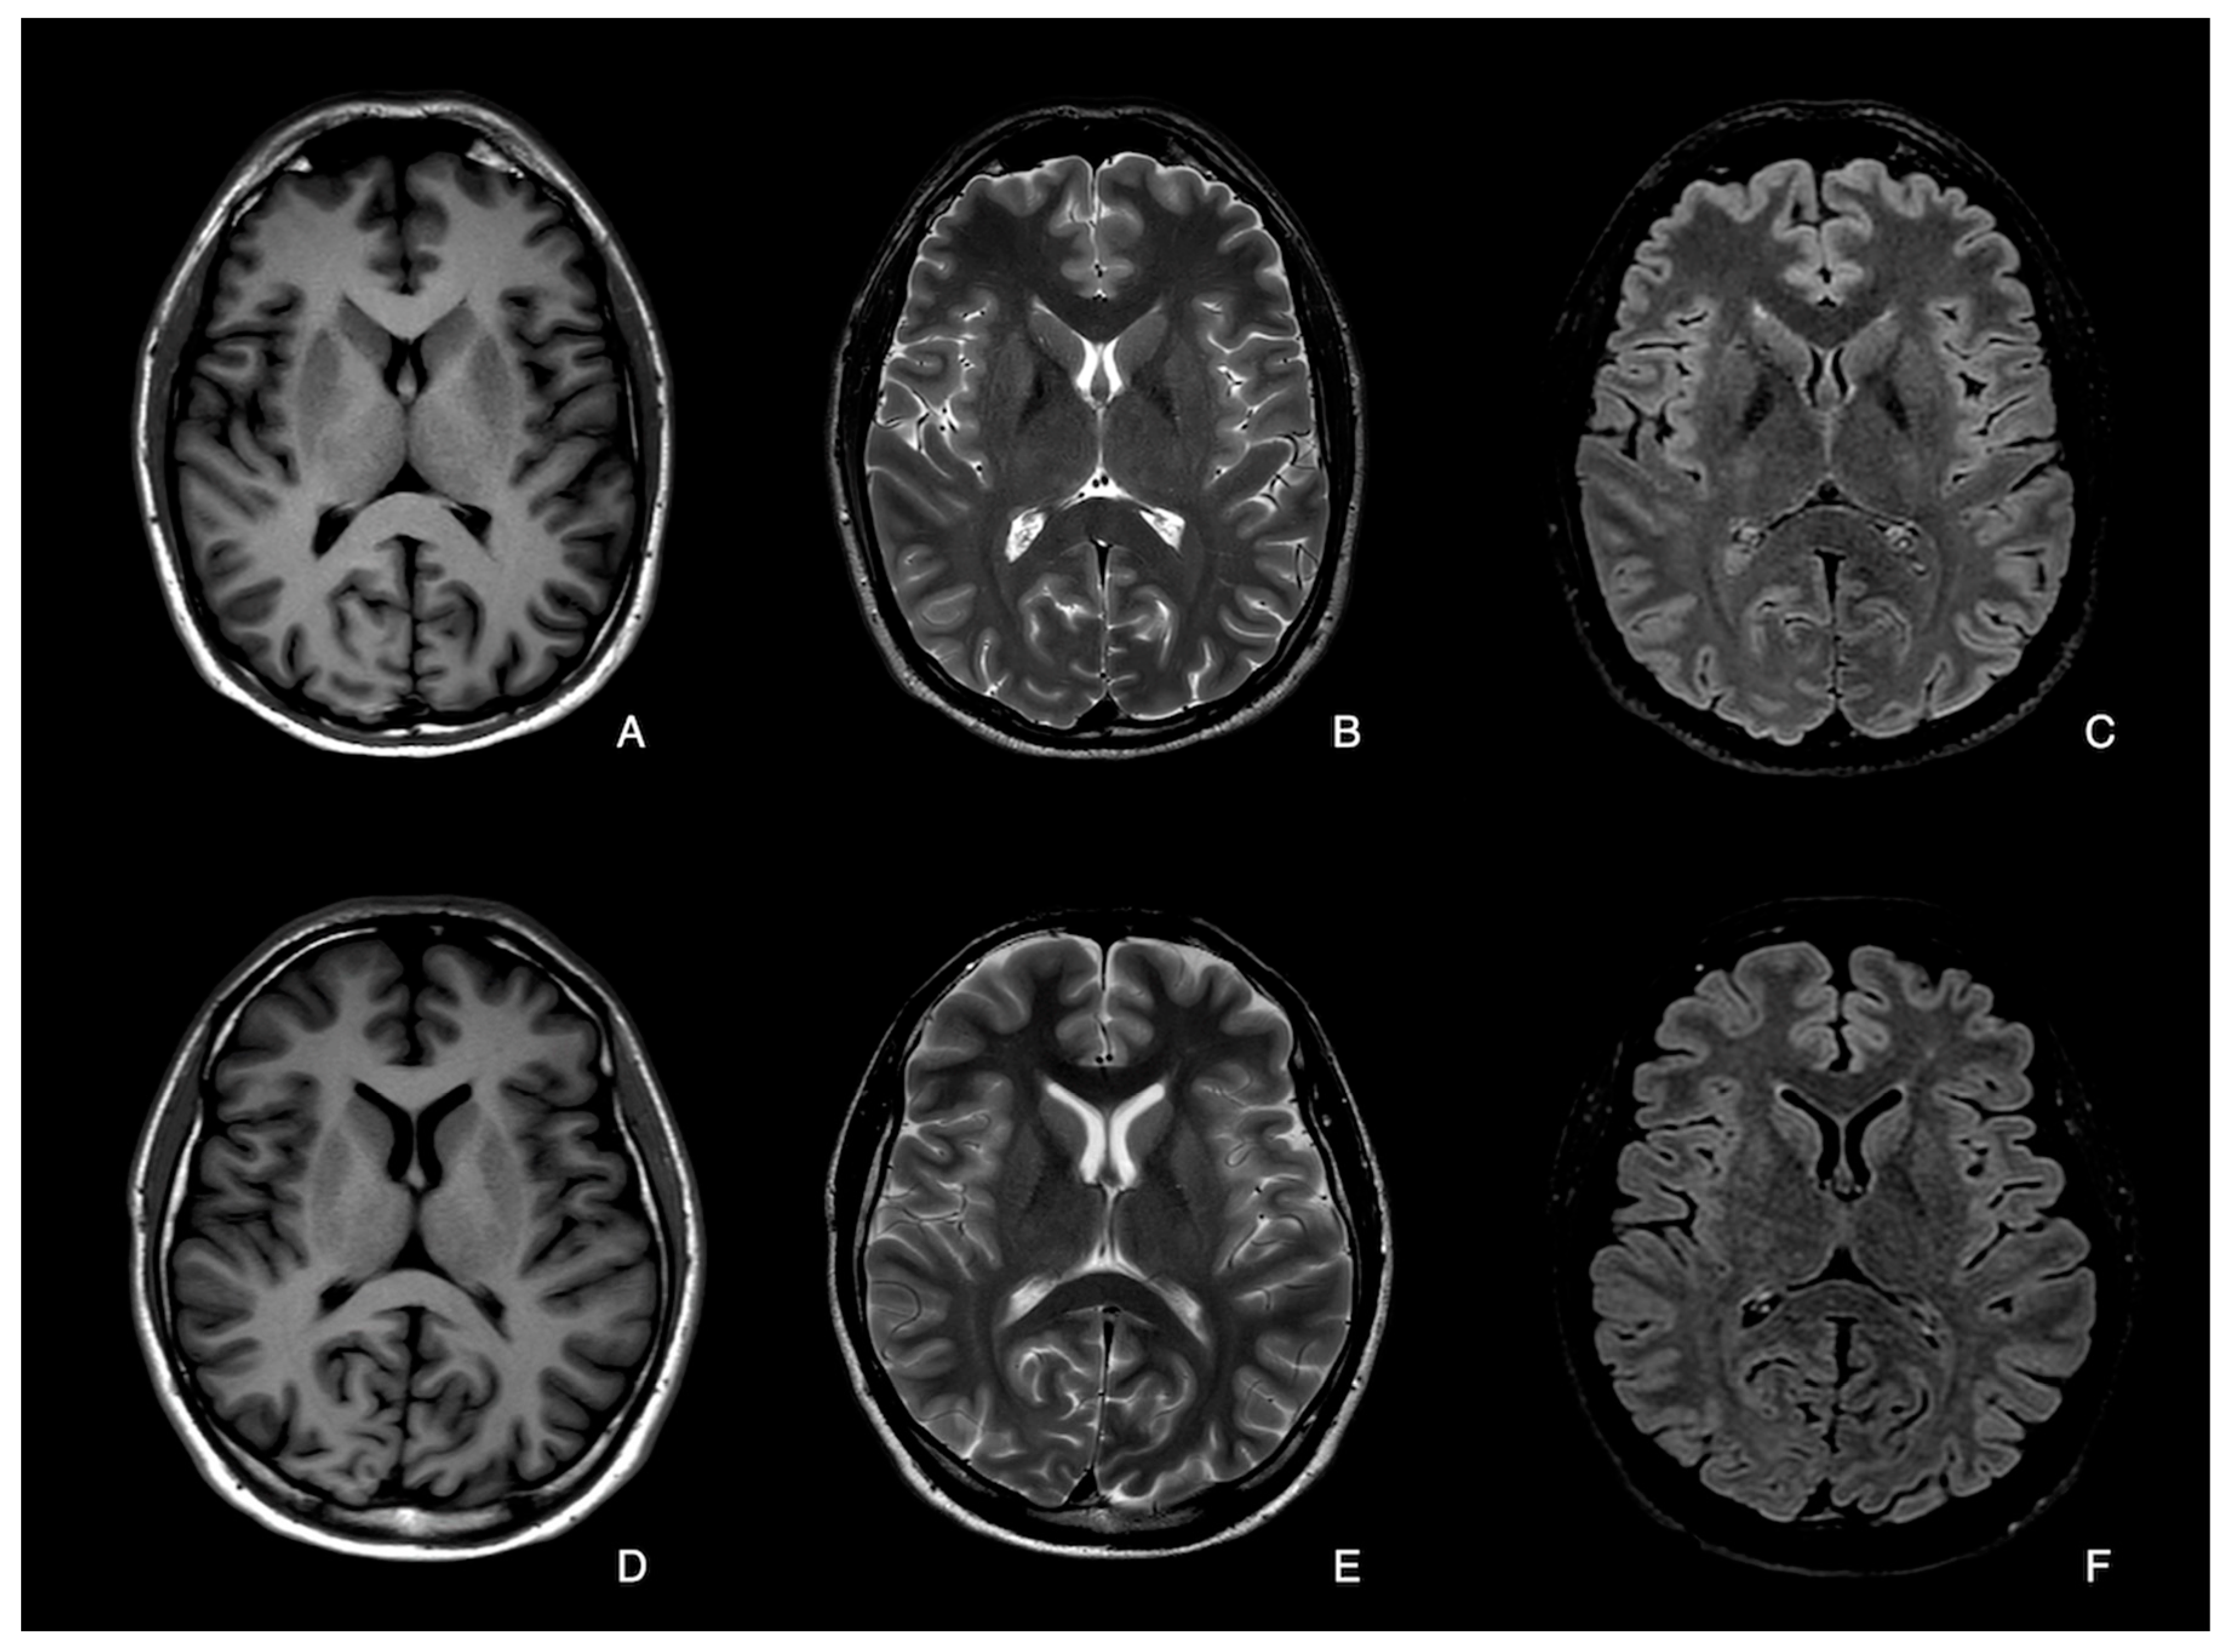

3.1. Qualitative Image Analysis